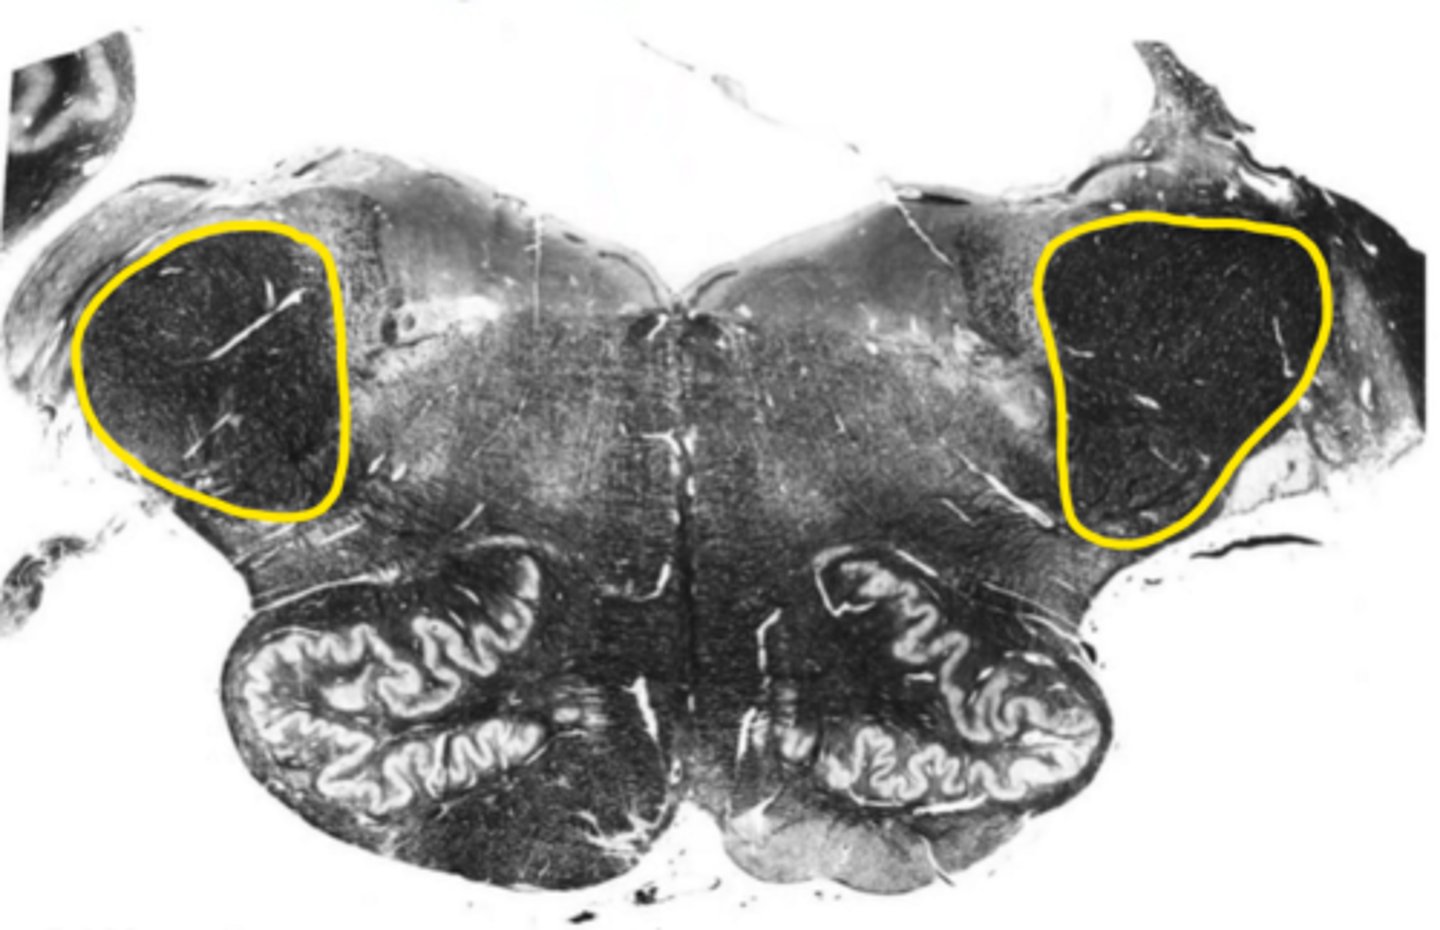

superior cerebellar peduncles

ID the structure

inferior cerebellar peduncles

open medulla

ID the brainstem level